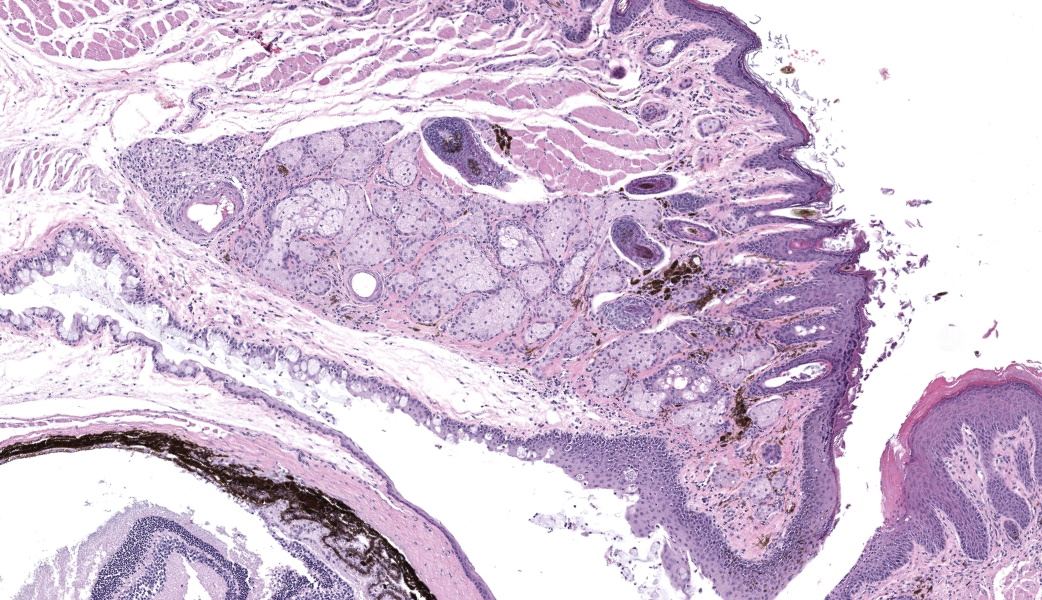

Bilaterally or unilaterally*, the eyelids contained locally extensive epidermal acanthosis and ortho to parakeratotic hyperkeratosis of varying severity. This was accompanied by epithelial erosion and mild serocellular crusting. There was mild to moderate mixed neutrophilic to lymphocytic inflammation within the conjunctiva and eyelid sebaceous glands (Meibomian glands). Focally there was occasional dilation and mild degeneration of Meibomian gland acini or ductules. The cornea, lens, iris, retina, optic nerve and other interior structures of the eyes were normal.

The Harderian gland was mildly enlarged (section plane-dependent) and glandular lumens contained occasional brown pigmented inspissated material (porphyrin secretions). Glandular epithelium lacked atypia and there was no compression or invasion as might be seen with adenoma or carcinoma.

- Eyelids: Blepharoconjunctivitis, neutrophilic, with epidermal acanthosis, erosions, and ortho to parakeratotic hyperkeratosis, unilateral to bilateral, moderate, chronic.

- Harderian gland: Hyperplasia with inspissated porphyrin secretions, bilateral, mild, chronic.

- Eyelid: Blepharoconjunctivitis, unilateral, lymphocytic and neutrophilic, chronic, diffuse, mild, with epidermal hyperplasia and erosion.

- Eyelid, Meibomian gland: Adenitis, lymphoplasmacytic, chronic, focal, mild.